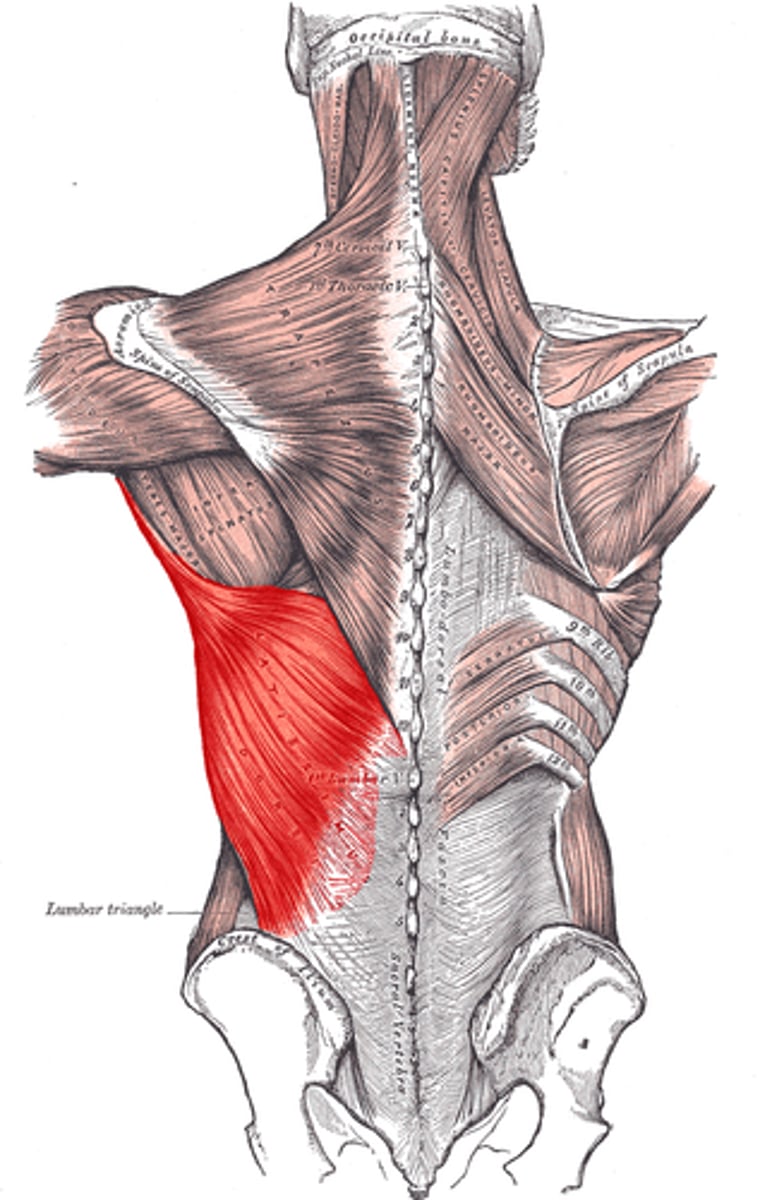

(Posterior axioappendicular and scapulohumeral muscles:) Superficial posterior axioappendicular muscles (extrinsic shoulder)

Trapezius and Latissimus dorsi

(Superficial posterior axioappendicular muscles (extrinsic shoulder):) Latissimus dorsi

-Extends, adducts, and medially rotates humerus

-Thoracodorsal n. (C6 - C8)